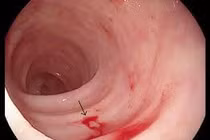

Viêm loét dạ dày tá tràng không được phát hiện sớm có thể dẫn đến nhiều biến chứng nguy hiểm, trong đó có xuất huyết tiêu hóa... Tuy nhiên bệnh hoàn toàn có thể điều trị khỏi.